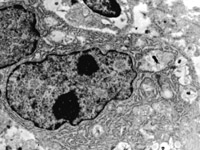

5-2-2 傷后第1天,毛細(xì)血管內(nèi)皮細(xì)胞核固縮,管腔內(nèi)血液凝集和瘀滯  TEM×6000

5-2-5 傷后第5天,膠原纖維相互融合,其間的細(xì)胞已崩解  TEM×6000